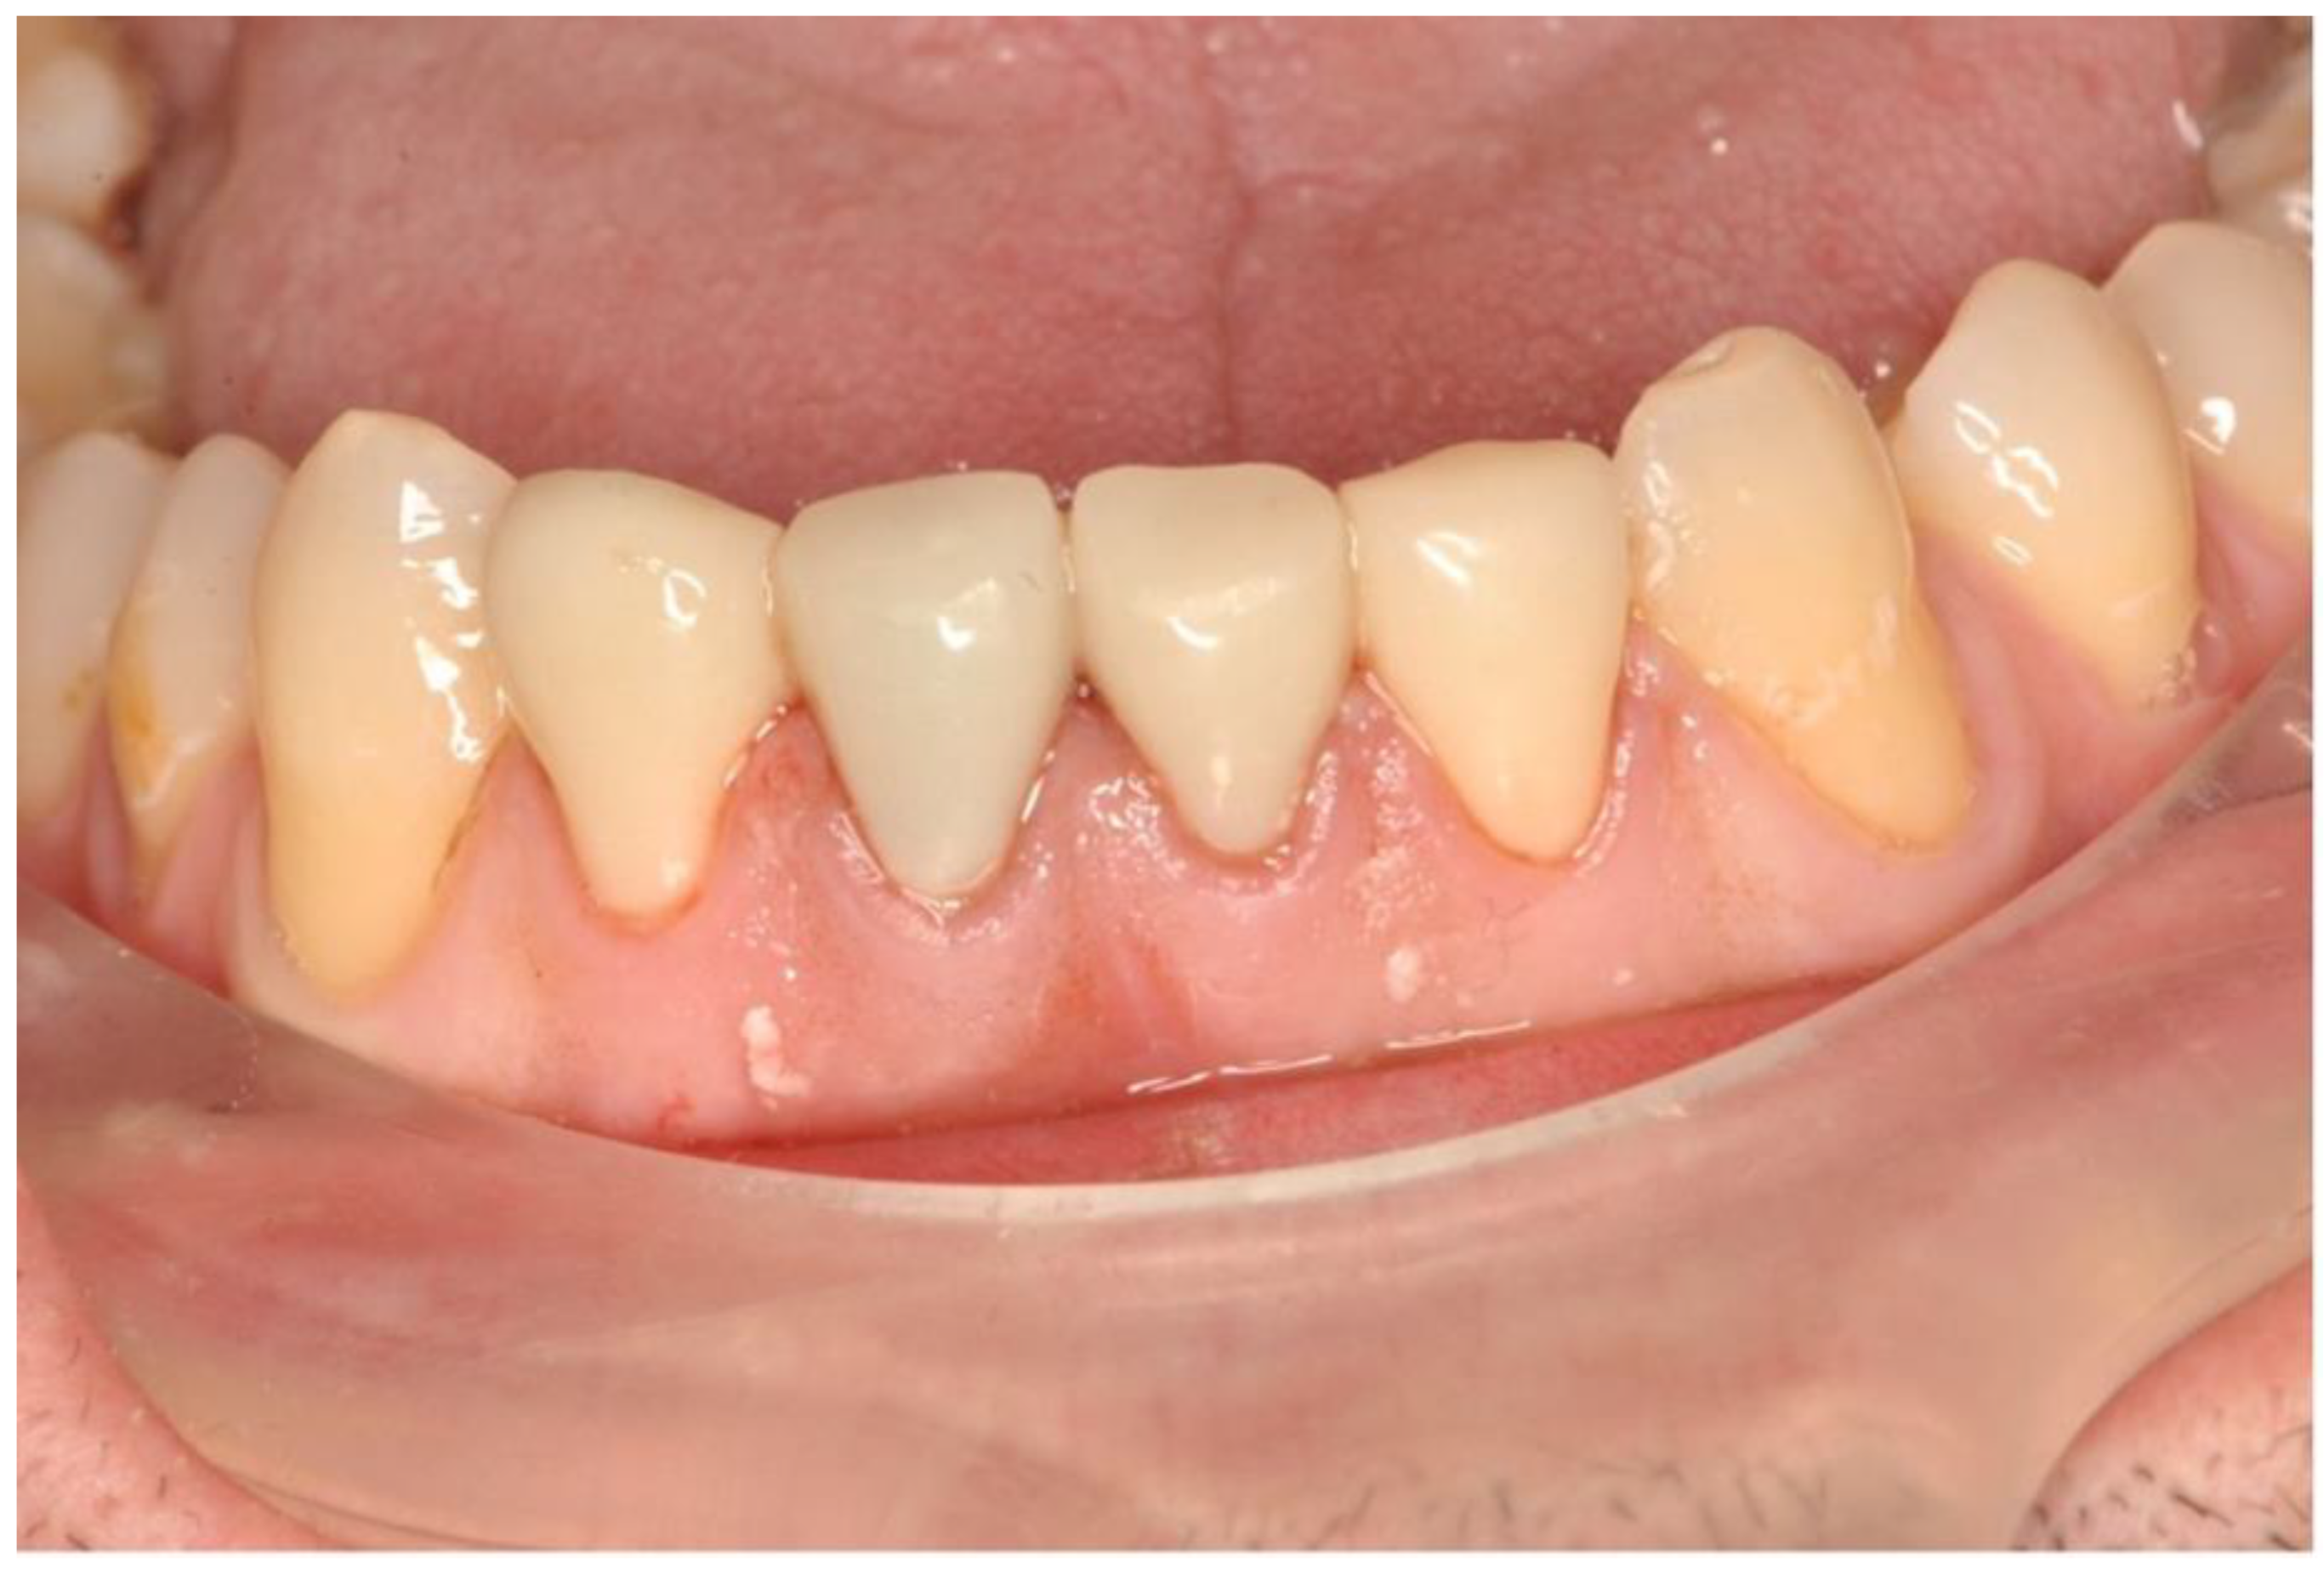

3. Clinical Procedure and Outcome